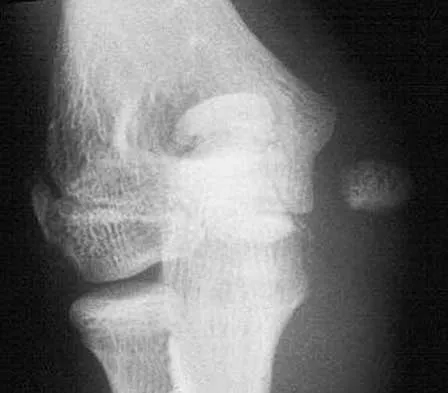

Figure 31 shows the AP and lateral radiographs of the elbow of a 56-year-old man with chronic polyarticular rheumatoid arthritis. His function continues to be limited by pain with activities of daily living. Examination shows that his total arc of motion is 110 degrees. Nonsurgical management has failed to provide relief. Treatment should now consist of

A semiconstrained prosthesis can provide excellent results in carefully selected patients. Because the radiographs show extensive joint destruction with loss of the capitellum and trochlea, a capitellocondylar total elbow (unconstrained) prosthesis is contraindicated. Elbow fusion is poorly accepted, and the radiographs show too much articular destruction for a radial head excision, synovectomy, or interposition arthroplasty to be effective. Ewald FC, Simmons ED Jr, Sullivan JA, et al: Capitellocondylar total elbow replacement in rheumatoid arthritis: Long-term results. J Bone Joint Surg Am 1993;75:498-507.